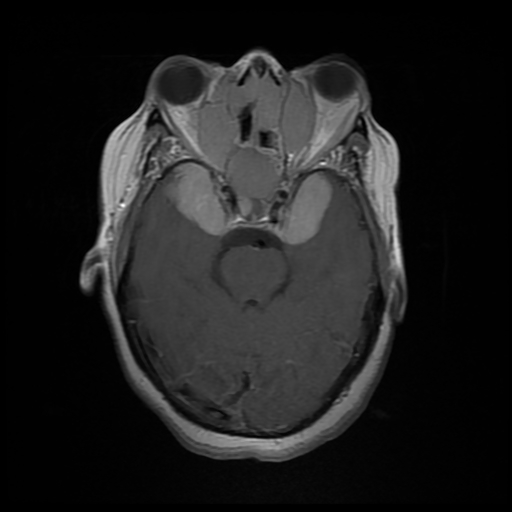

What syndrome is this finding associated with

http://www.ajnr.org/content/35/11/2186

Di George

CATCH22

C - cavum septum pelucidum, cleft palate,

A - Abnormal Facies (hypertelorism, low set ears, short philtrum, among others)

T - Trunchus ateriosus, Thymic Hypoplasia

C - cardiac anomalies

H - hearing problems. Middle ear malformations. Hypoparathyroidism

22 - Microdeletion of 22q11.2